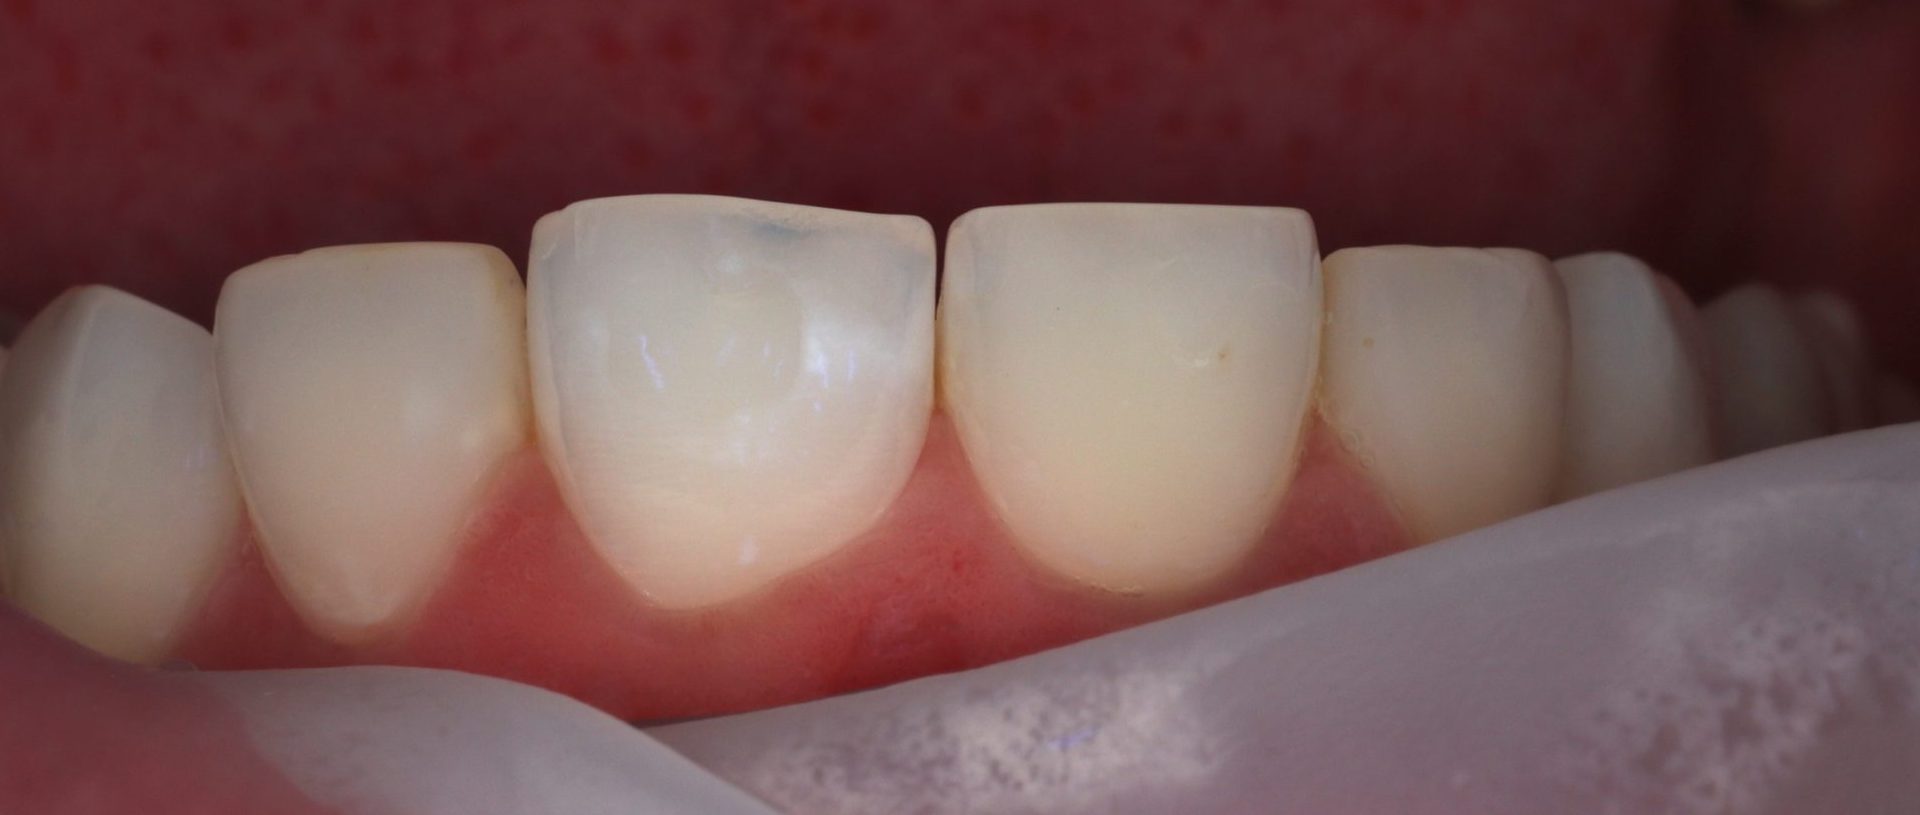

Během nošení rovnátek je čištění zubů složitější, zejména v okolí zámečků. Právě tam může postupně docházet k demineralizaci skloviny. Sklovina se jemně oslabí a vzniknou v ní drobné mikropóry. Tyto změny nejsou vždy hned vidět. Často se projeví až ve chvíli, kdy se rovnátka sundají a povrch zubu je znovu celý odkrytý. Zub pak může působit bělavě, někdy až „křídově“, přestože je jinak zdravý.

Během ošetření se povrch skloviny chemicky připraví tak, aby se otevřely mikropóry. Následně se do nich aplikuje tekutá infiltrační hmota, která tyto póry vyplní. Jakmile v nich není vzduch, ale infiltrační materiál, změní se index lomu světla. Světlo začne sklovinou procházet rovnoměrněji a bílé skvrny se opticky ztratí nebo výrazně zeslabí.

Výsledek vždy závisí na rozsahu a hloubce demineralizace. V některých případech skvrny zmizí úplně, jindy mohou zůstat drobné nerovnosti. I tyto situace je však možné předem realisticky zhodnotit a vybrat vhodný postup léčby.